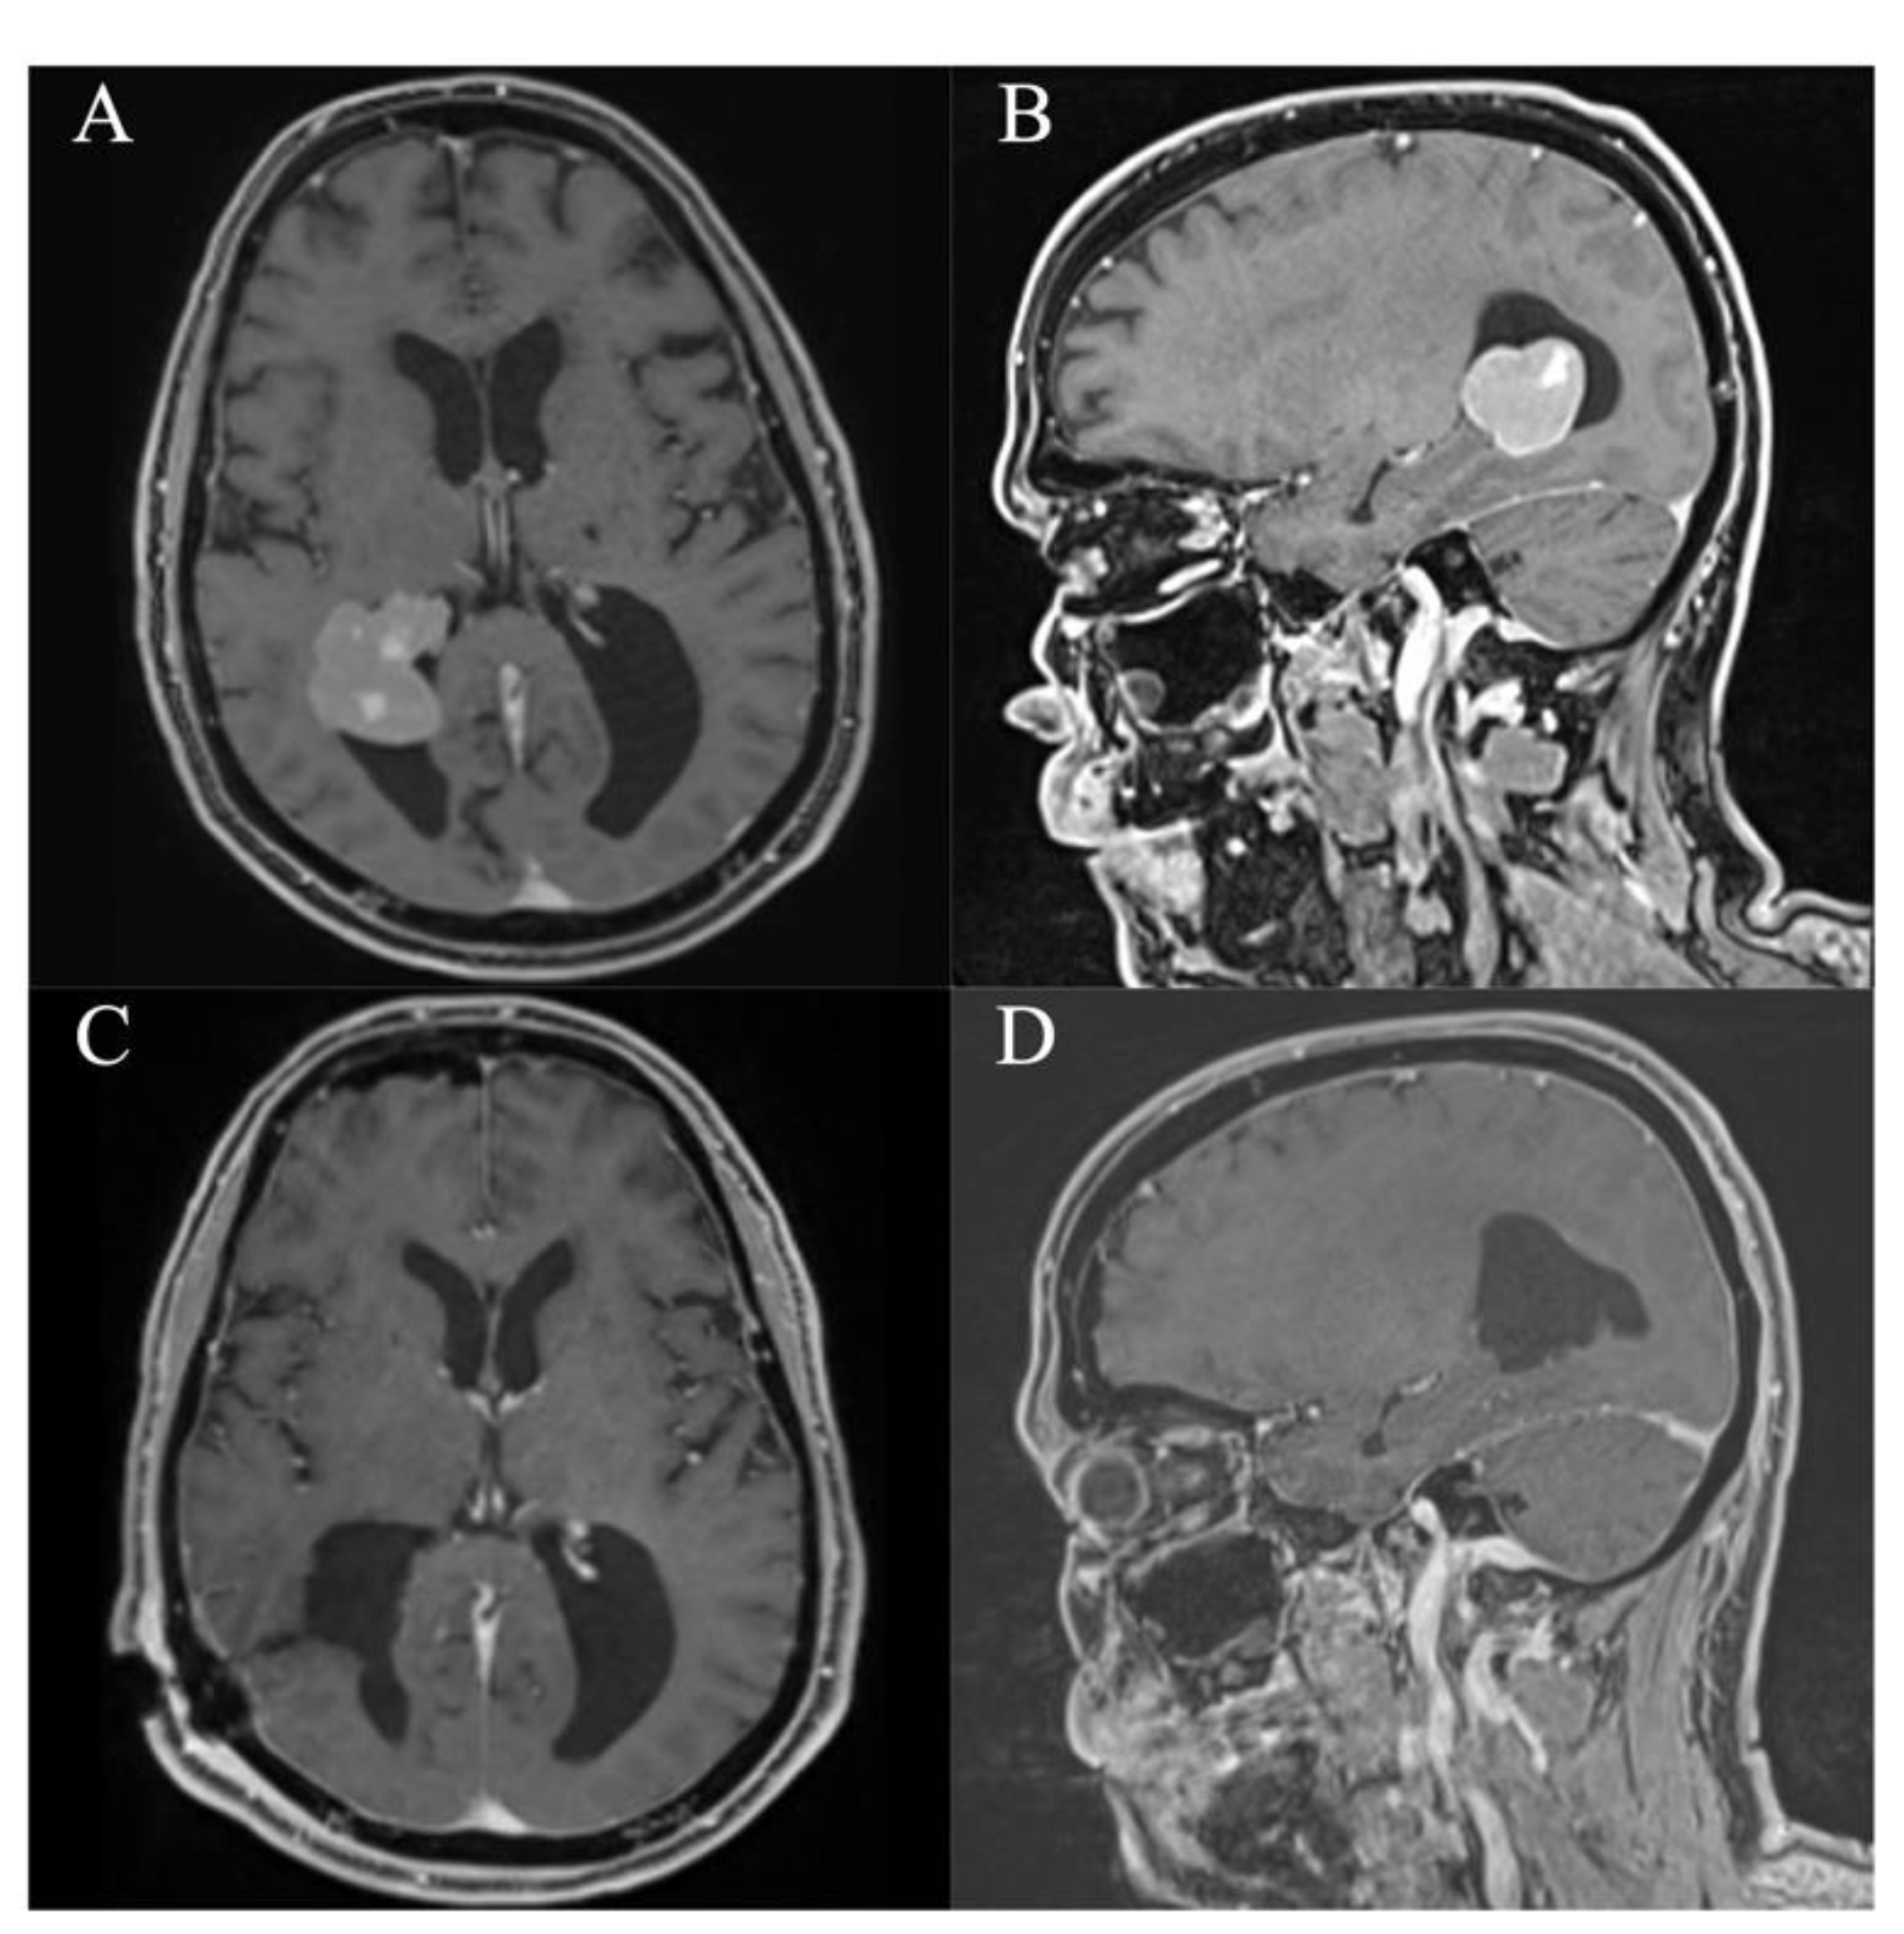

In all patients, a GTR/NTR could be achieved (Table 3). The pre- and postoperative scans of cases no. 3, 6, and 7, which were all treated through an EA approach and case no. 8, which was treated through a PE approach, are shown in Figure 3, Figure 4, Figure 5 and Figure 6. In one patient (case no. 5), due to her advanced age, we referred from resecting the vascularized capsule of the colloid cyst, achieving NTR. The mean surgery time was 163.6 ± 54.2 min (range 82–240 min) and the average blood loss was 142.5 ± 90.4 mL (range 50–300 mL). The PE approach was associated with lower mean blood loss than the EA approach (87.5 ± 47.8 mL vs. 197.5 ± 93.2 mL, p = 0.114). In four patients (50%), a total of six postoperative complications occurred, of which all were transient. Two patients (25%) showed transient cognitive impairments after resection of a colloid cyst, most likely directly associated with the endoscopic approach. The remaining four transient complications were unrelated to the use of endoscopy or NUA (Table 3). The two patients with neuropsychological evaluation showed postoperatively scores of 18/30 and 25/30 points, respectively, with a documented improvement in both patients at follow-up (18/30 to 24/30 points within 35 days and 25/30 to 30/30 points within 114 days). With regards to the remaining adult patients, no evaluation was carried out, because there was no evidence of neurocognitive deficits subjectively. In the two children with intraventricular lesions, no postoperative neurocognitive assessment was performed (due to autism disorder in the context of tuberous sclerosis in one case and due to the very young age of 5 months in the other case) (Table 3). At follow-up (15.9 ± 6.3 months; range 6.8 to 23.2 months), all patients showed improved or unchanged mRS when compared to the mRS at discharge. Complete regression or improvement of the preoperative complaints was seen in all patients, while MRI at follow-up showed no recurrence in any of the cases (Table 3).

Figure 5. Case 7. Axial and sagittal MR images, T1-weighted sequences with contrast medium preoperatively (A,B) and immediately postoperatively (C,D) after resection of the intraventricular subependymal giant cell astrocytoma via a right frontal endoscopic-assisted approach. It shows a gross total resection with residual blood in the resection cavity. Furthermore, there are pre-existing subependymal tuberosities in both lateral ventricles.